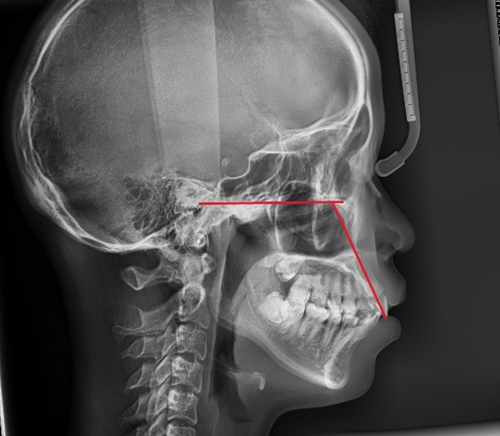

돌출입인지 아닌지를 판단하는 기준은 여러 가지가 있으나, 그 중에서 가장 간단한 방법 중 하나는 측면에서 코 끝과 턱 끝을 일직선으로 연결했을 때 입술의 위치를 평가하는 것입니다.

입술이 그 라인보다 앞쪽에 있다면 돌출입으로 판단할 수 있습니다.

돌출입의 유형은 크게 3가지로 나눌 수 있습니다.

첫째, 골격성(턱뼈 자체가 튀어나온) 돌출

둘째, 치아 각도가 뻐드러진 경우

셋째, 위 두 가지가 복합적으로 나타나는 경우

치성 돌출